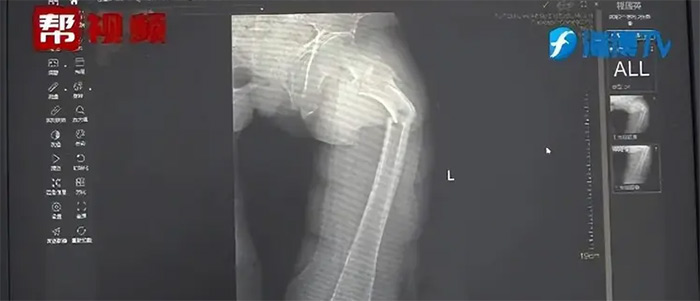

และผลจากการเอกซเรย์ก็พบว่า กระดูกต้นขาของนายยีหักเป็น 2 ท่อน และการที่บอกว่ากระดูกหักเพราะไอก็ไม่เป็นเหตุเป็นผล อีกทั้งยังไม่มีสัญญาณใด ๆ ที่บอกว่าเขาประสบอุบัติเหตุ นายจงจึงเรียกทีมแพทย์มาปรึกษา และซักประวัติสุขภาพ พฤติกรรมการรับประทานอาหาร รวมทั้งยังทดสอบถึงความหนาแน่นของกระดูก และผลการทดสอบก็ออกมาน่าตกใจ เพราะความหนาแน่นของกระดูกของนายยีนั้น ไม่ต่างจากคนอายุ 80 ปี